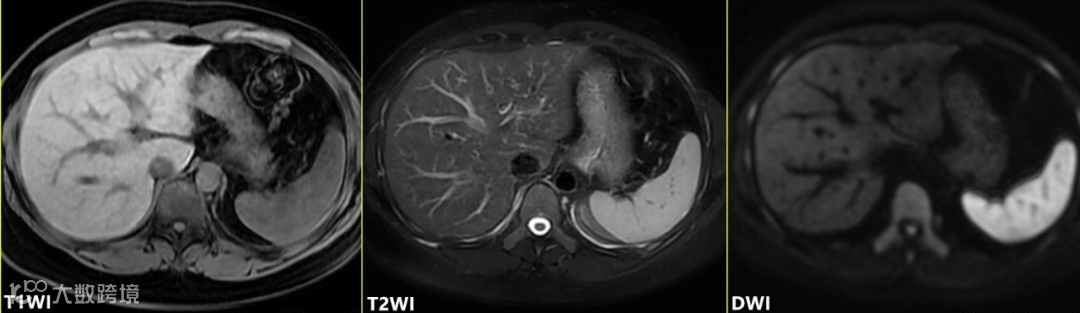

脾脏在MRI的表现:

T1WI信号低于肝实质,T2WI信号高于肝实质(接近于肾皮质);

在DWI上呈明显高信号。

动脉期不均匀显著强化,门脉期以后均匀强化。